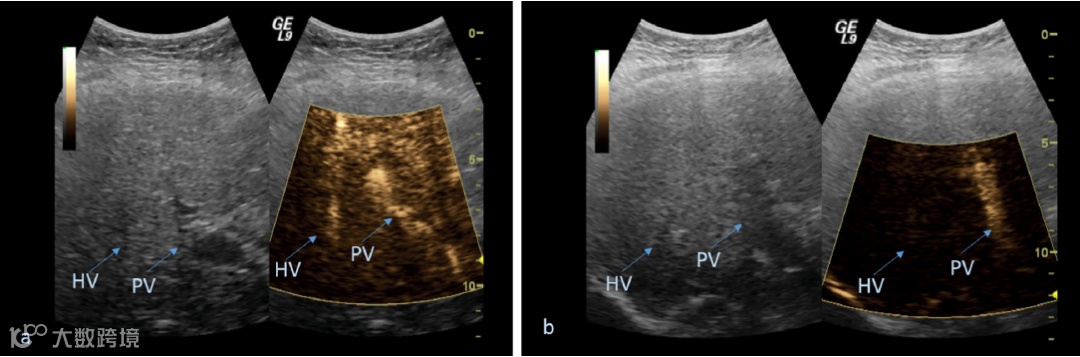

次谐波辅助压力评估(SHAPE)是基于超声造影微泡的次谐波幅度与环境压力之间存在的反比关系。近日,来自美国德雷塞尔大学的Gupta I等人研究了SHAPE监测门静脉高压患者疾病进展方面的准确性,相关研究内容发表在Academic Radiology杂志上。

使用带有4C curvi-linear探头的改进型Logiq 9扫描仪(GE,Waukesha,WI)通过Sonazoid (GE Healthcare, Oslo, Norway; FDA IND 124 465)获取患者的SHAPE数据(分别在2.5和1.25 MHz上进行发送和接收)。按照肝静脉压力梯度≥10 mmHg的标准,在178例患者中确定了21例患者存在有临床显著性门静脉高压(中位年龄59岁,12名男性)。每6.2个月重复进行一次SHAPE检查。通过肝功能检查和临床相关指标确定患者的治疗反应。

结果发现,在21名门静脉高压患者中有11名进行了成功随访,平均随访时间为6.2个月。与单一无反应组患者相比,归为治疗反应组的患者中(n=10; -4.01±3.61 dB),SHAPE信号的减少更为明显(2.33 dB;P<0.001)。该结果与终末期肝病(MELD)评分模型、改善门静脉高压的根本原因、肝功能检查改善和腹水减少的临床结果相对应。

因此,SHAPE可用于监测门静脉高压患者的病情进展,有助于临床医生对患者进行日常管理,但尚需更大规模的研究进一步验证该结论。

临床显著性门静脉高压是指肝静脉压梯度(HVPG)>10 mmHg,其与静脉曲张、食管出血、肝失代偿、术后失代偿和肝细胞癌的风险增加有关。直接测量HVPG是门静脉高压诊断的金标准,但需要特定的专业知识,且需要一定花费,难于做到在临床实践中动态监测。无创超声测量肝脏硬度弹性与测量脾脏大小和血小板计数相结合,对临床显著性门静脉高压的初步诊断具有高度预测性,但对治疗过程中HVPG变化的监测价值尚不确定。因此,临床上亟需一种可靠的、经济有效的、无创性的评估门静脉压力的方法来监测门静脉高压的治疗效果。

本研究采用SHAPE超声检查技术,旨在评估门静脉高压患者在利用SHAPE技术监测门静脉高压治疗效果中的敏感性。SHAPE新技术不依赖常规成像参数,而是利用超声造影剂的次谐波发射与环境压力之间的逆线性关系,有可能作为一种节省成本、高效的门静脉压力监测工具。

尽管SHAPE技术存在优势,本研究也有一定的局限性,如:研究随访患者仅11例,且跟踪随访患者每6个月需重复一次检测,这需要患者具有良好的依从性。总之,研发一种能够动态监测门静脉压力改变的无创技术很有前景,对于临床上治疗门静脉压力的药物研发和应用具有重要意义。